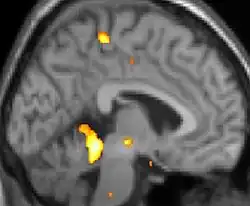

| Positron emission tomography (PET) shows brain areas being activated during pain. | ||

Positron emission tomography (PET) scans indicate the brain areas which are activated during attack only, compared to pain free periods. These pictures show brain areas that are active during pain in yellow/orange color (called "pain matrix"). The area in the center (in all three views) is activated only during cluster headaches. The bottom row voxel-based morphometry shows structural brain differences between individuals with and without CH; only a portion of the hypothalamus is different.[37]